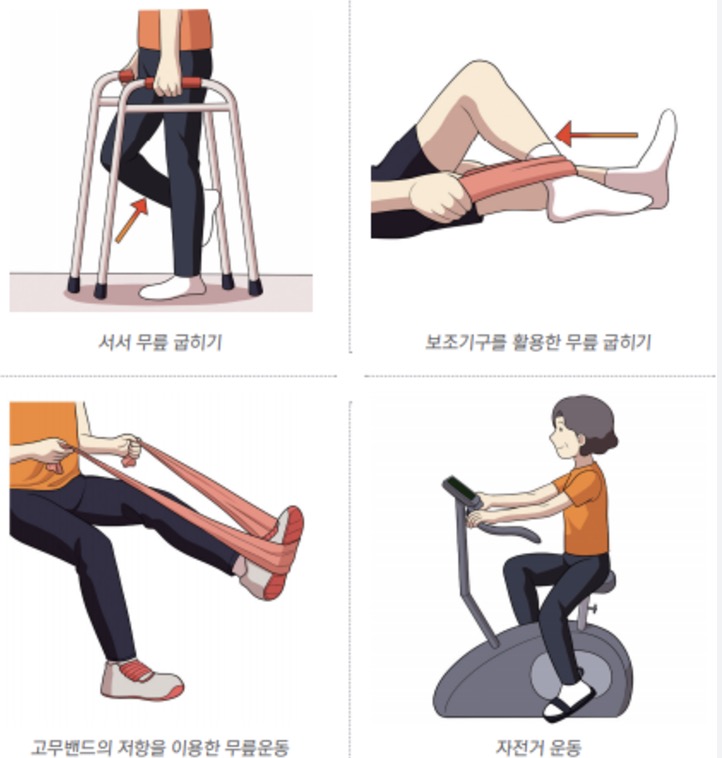

3. 실내에서 할 수 있는 관절 운동

추운 겨울철에도 실내에서 안전하게 할 수 있는 관절 운동을 소개합니다:

- 앉았다 일어나기 운동 (하루 10회씩 3세트)

- 다리 들어올리기 (각 다리 15초씩 유지)

- 무릎 굽혔다 펴기 (20회씩 3세트)

- 발목 돌리기 운동 (각 방향 10회씩)